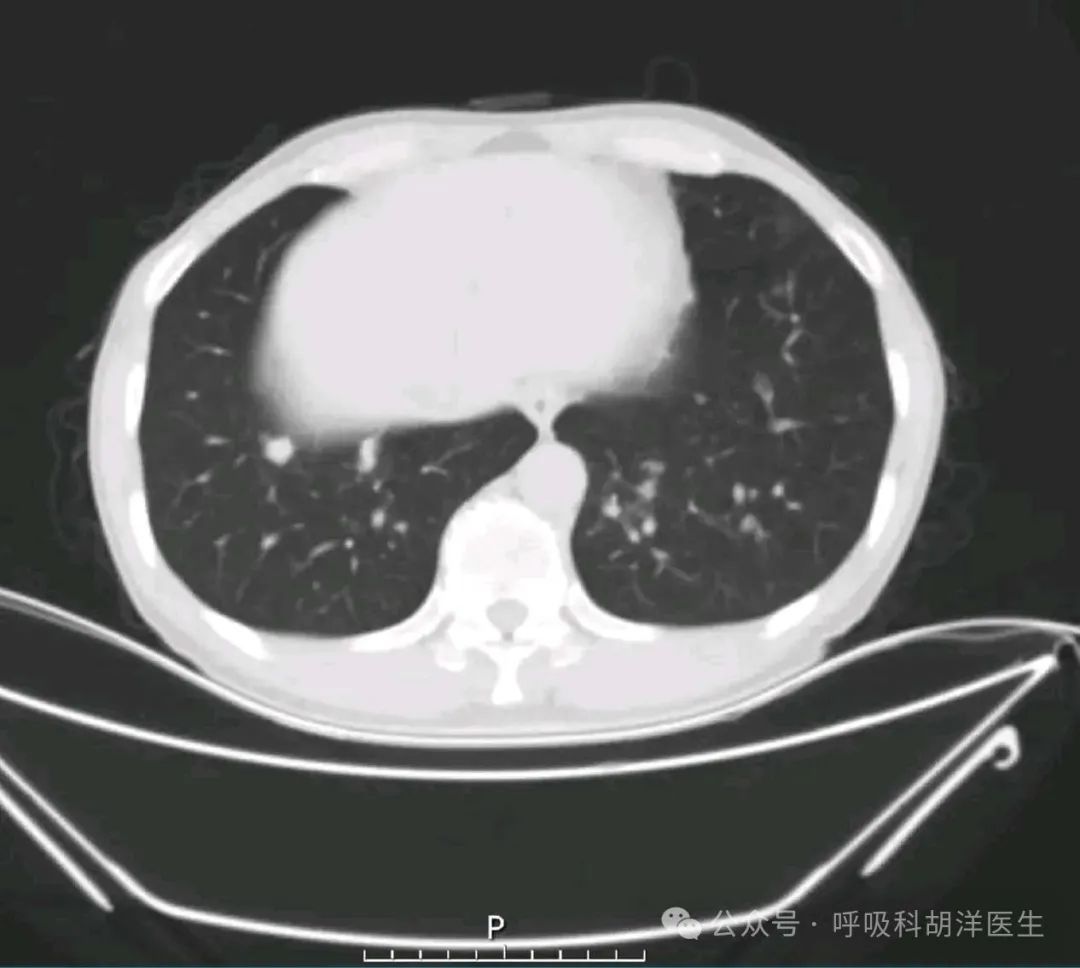

那如何选择ct检查呢?说到这,就一定要了解ct的分类, Ct分低剂量ct,普通平扫ct,增强ct,高分辨率ct等等。低剂量ct顾名思义就是辐射剂量较低的ct,这个通常用于健康人群的体检筛查,普通ct的分辨率比低剂量ct要高一些,对于小的结节来说,做普通ct就可以了,要想追求更高的分辨率,观察结节的细节的话,最好用高分辨率ct,目前分辨率最高的是1024的ct,这个一般只做结节局部的扫描,不做全肺的扫描,因为辐射剂量比较大。另外就是普通的高分辨率ct,当然,我们低剂量ct也可以调整成高分辨率的模式,但这种模式还是不如普通剂量的高分辨率ct来的清晰。

所以如果以前没有做过ct的人群体检的话,做低剂量ct是最合适的。增强ct一般用于比较大的肿块检查,他主要是看病灶内部血管的丰富程度的,并不是说分辨率更清晰,对于比较小的结节做增强ct没有太大的意义,一般做分辨率比较高的ct就可以了。